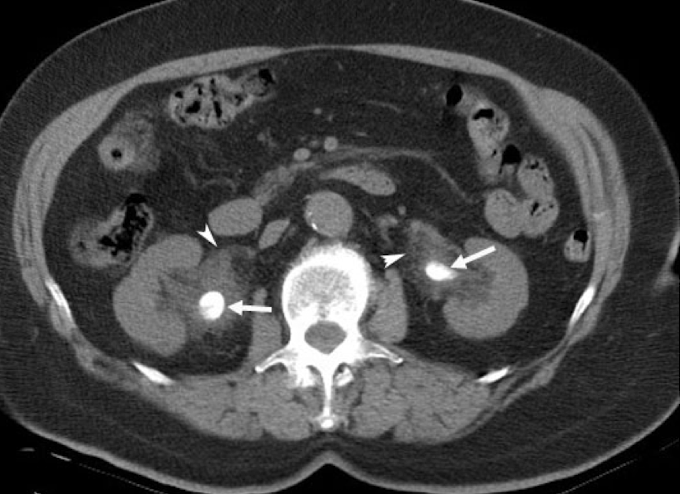

Pyelonephritis

CT Abdomen/Pelvis IV contrast

Renal cell carcinoma

CT Abdomen/Pelvis IV contrast

CT abdomen non-contrast

What imaging is used to visualize gallstones?

CT urogram

Which imaging is used to visualize ureteral stricture?